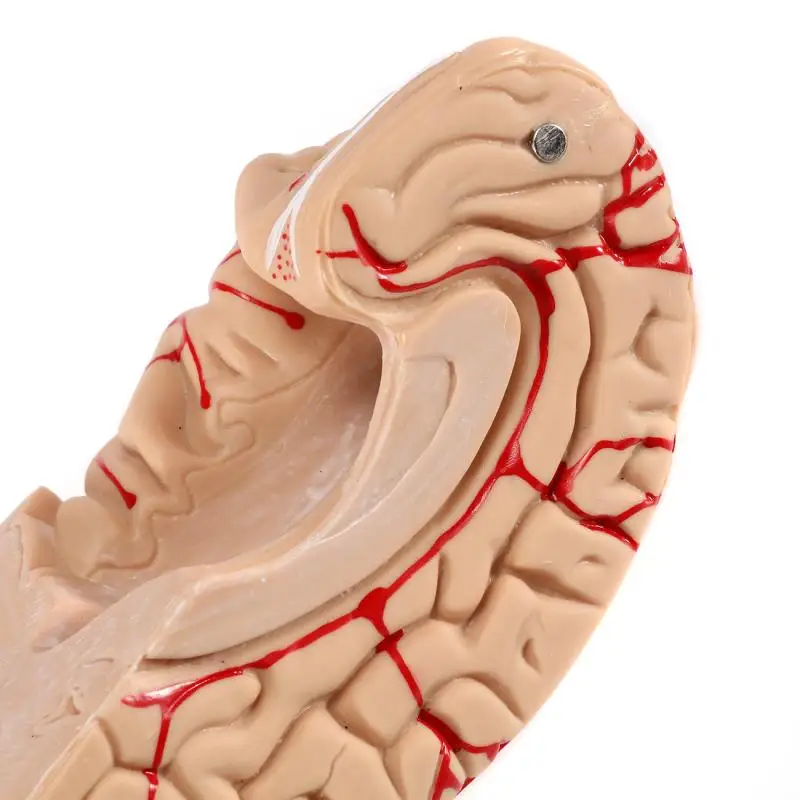

Анатомия: Задняя соединительная артерия мозга

Раздел: Фотоэссе